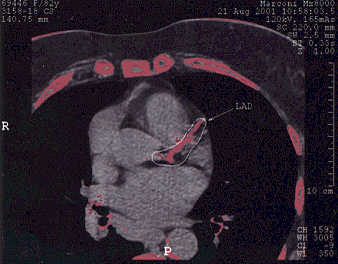

# 3 FL: Avoiding Angiography in an Octogenarian

This turned out to be a good

idea. FL tolerated four months of

NanobacTX well; angina frequency fell from 5 to 1 episode per week, NTG is no

longer required, and FL was able to increase her activity level considerably.

Her CT score fell by 26%, fibrinogen fell by 30 points, and her

cardiac-CRP value plummeted. Following an additional two months of treatment, FL's score

fell an additional 36%, so at the six month point, FL's score has fallen by

53% from baseline. A dobutamine stress echo (chemical stress echo)

demonstrated the old heart attack that we knew about, but no new abnormalities

were brought out. Subjectively and objectively FL improved. The

baseline and six month scans are shown below; with your own eye you can see the

difference in the extent of LAD calcification. FL is going to continue on NanobacTX, aiming for

complete decalcification.